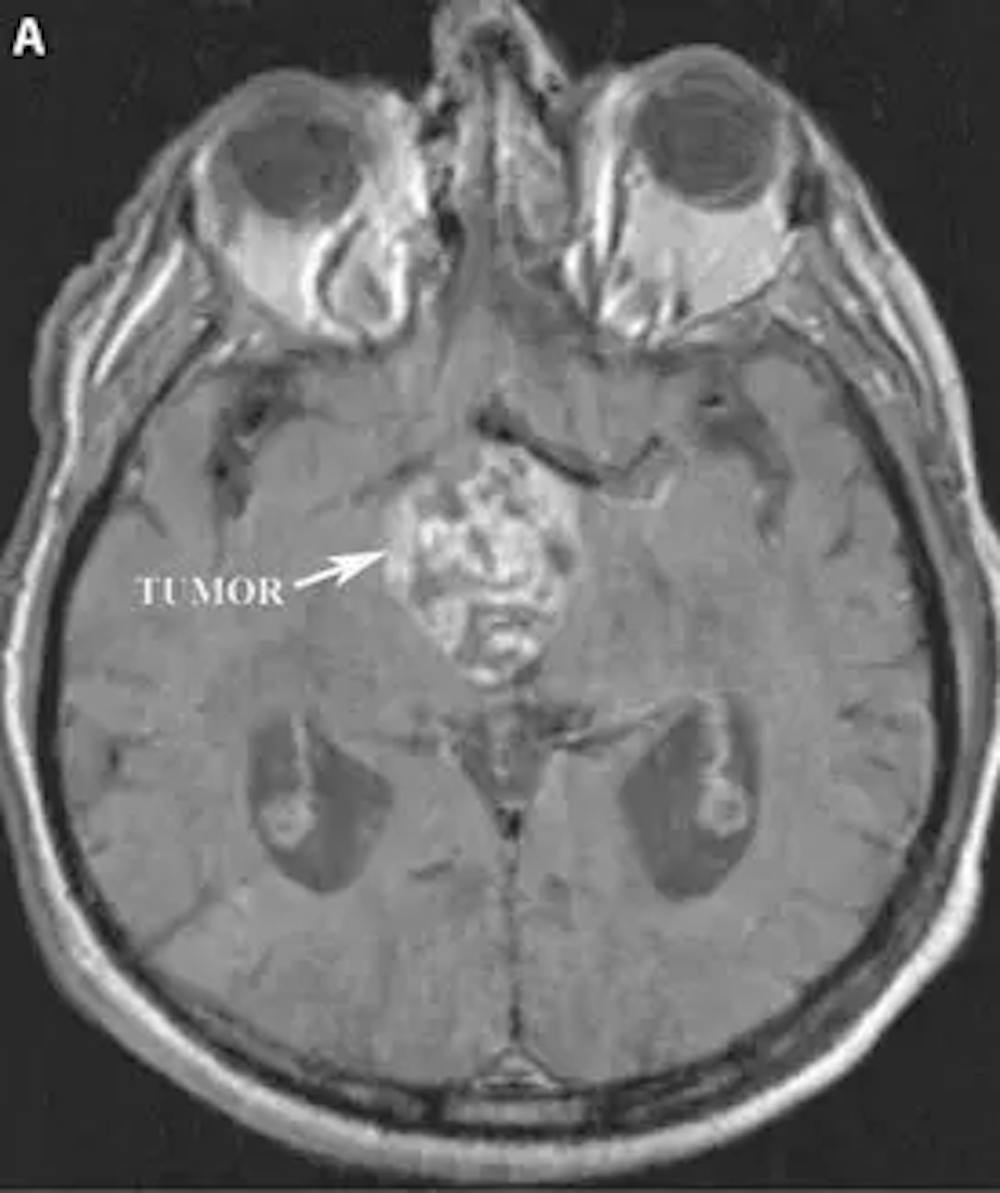

A) RM axial ponderada em T1 pré-operatória do cérebro com contraste demonstrando o craniofaringioma com realce localizado no terceiro ventrículo.